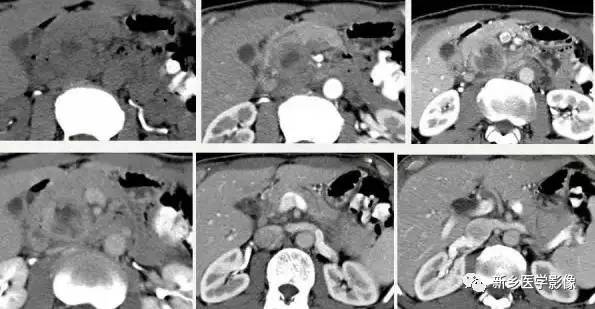

CT 、M RI 上, 本病表现为胰腺边界清楚的大肿块, 囊实相间, 实性部分主要位于病变周边,有强化;囊性部分主要位于病灶中心区域, 囊变区密度较高, CT 值40 ~50Hu 。30 %的患者病变周边可见钙化。

由于病变内常有出血,T1W I 上可见不均匀高信号, T 2WI 上见不均匀低信号 。M RCP 或E RCP 示胰管受压、移位或中断。